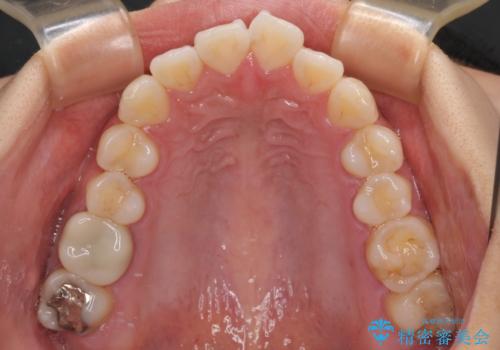

- 前歯が突出して、眠るときに口が開いてしまうことを気にして来院された患者様です。

横から見た際の口元の飛び出した印象も改善したいとのことで、上下左右の第一小臼歯4本を抜歯し、ワイヤー装置にて抜歯矯正を行うこととしました。